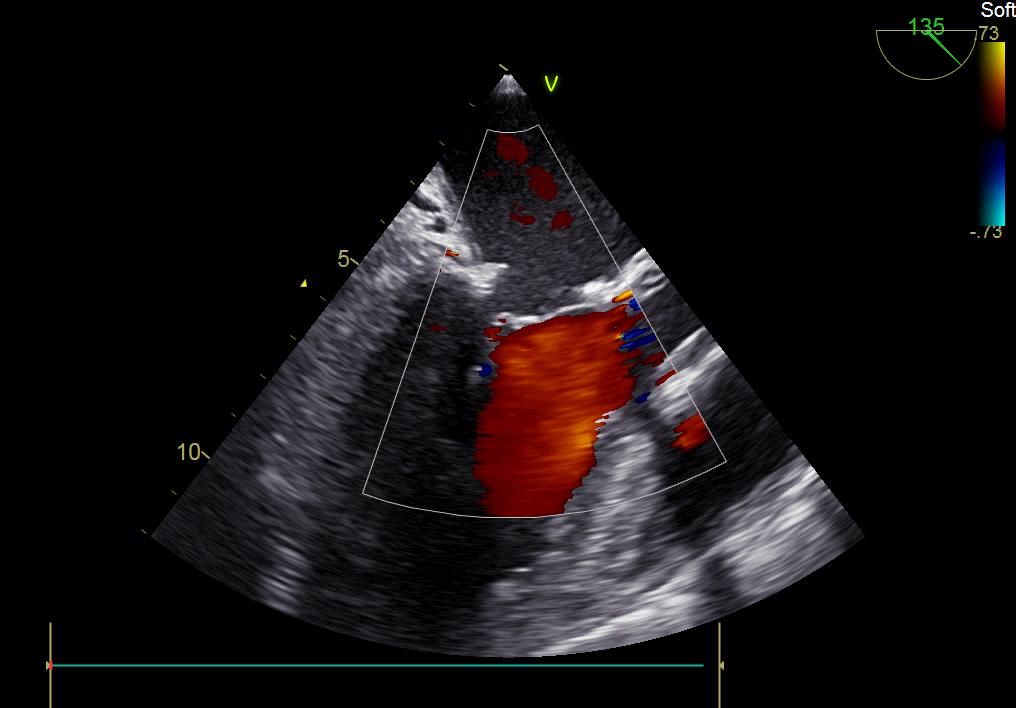

患者何某,42歲男性,因心功能不全入住我院心胸外科,心臟彩超提示二尖瓣后葉脫垂伴有重度返流及心臟擴大,在迅速糾正心衰后,手術(shù)便提上日程,心胸外科廖金文主任多次組織全科及兄弟科室討論,在二尖瓣置換及成形術(shù)上,最終決定采取二尖瓣成形術(shù)。為保證手術(shù)安全,討論圍手術(shù)期各個細節(jié),所謂細節(jié)決定成敗,因為術(shù)前的細致全面,加上術(shù)中的一絲不茍及術(shù)后的精細化管理,患者術(shù)后恢復(fù)順利,健康出院,復(fù)查心臟彩超未見二尖瓣返流。

術(shù)后彩超